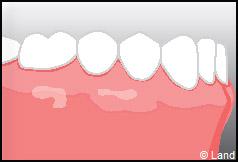

Aussi, pour corriger ces défauts, on fait appel à la chirurgie muco-gingivale.

Une classification descriptive de ces récessions permettant la possibilité de recouvrement par cette chirurgie a été clairement décrite.

Les conséquences de cette mise à nu de la racine dentaire sont multiples, le patient peut présenter une hypersensibilité dentaire et l’aspect de ces récessions peut être inesthétique. Dans ce cas, la chirurgie muco-gingivale est recommandée et elle peut se faire de différentes façons.